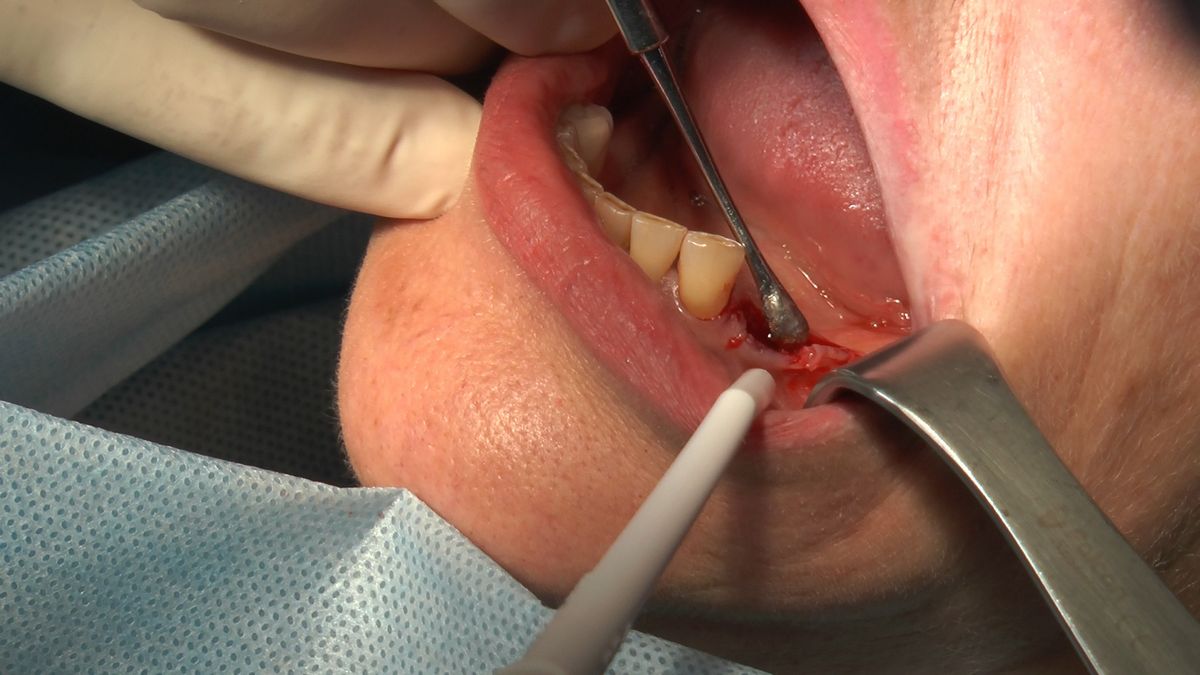

W ostatni weekend czerwca 2018 roku kursanci II Sezonu Preludium Implantologii odbyli piątą, finałową sesję, która w całości podporządkowana była praktyce. W ciągu dwóch dni zabiegowych Lekarze uczestniczący w szkoleniu przeprowadzili szereg zabiegów pod kierunkiem dr n.med. Violetty Szycik. Wszczepili 17 implantów oraz przeprowadzili ekstrakcje i zabiegi regeneracyjne kości. Zabiegi były wykonywane także w sedacji dożylnej z udziałem specjalisty anestezjologii i intensywnej terapii dr Jolanty Grzybowskiej. Preludium implantologii to nowy program edukacyjny dla adeptów implantologii stomatologicznej, którego celem jest wprowadzenie do implantologii poprzez pozyskanie wiedzy w szerokim zakresie i uwzględnieniem szczegółów mających decydujące znaczenie dla powodzenia leczenia implantologicznego. Ale tak jak wszystkie szkolenia w Instytucie Vivadental, w tym wiodące Practiculum Implantologii, zorientowane jest na praktyce i samodzielnym wykonywaniu zabiegów pod kierunkiem Mentora. To najlepsza edukacja w medycynie zabiegowej, a zarazem najlepszy start do implantologii.